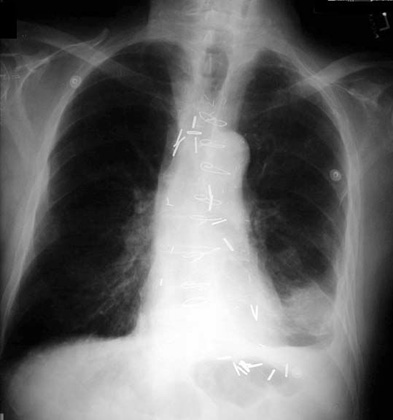

Esophageal surgical clips.